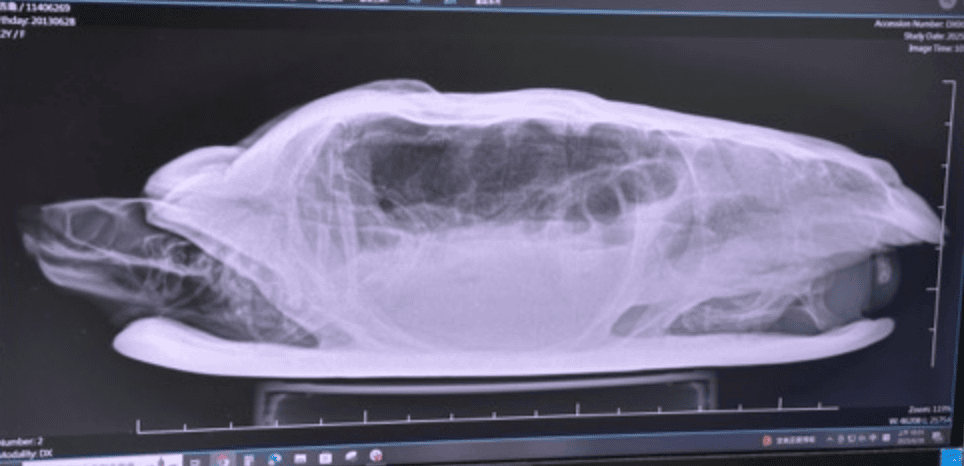

我在幫烏龜換水的時候,抓起烏龜但沒拿穩,我的巴西龜就從我手裡滑出去,背殼撞到陽台地板凸起的地方,大概從高度1公尺左右的地方摔到地上,烏龜背殼直接掉色,我用棉花棒擦拭隱約看到微微滲血,馬上預約看醫生,因為巴西龜的殼下面就是他們的肺,很怕會傷害到他的肺部!(從下圖可以看到烏龜的背殼左側偏上,有一小塊殼不見了)

由於上殼是肺,不確定有沒有傷害到肺部,醫生建議照X光,我的烏龜也獲的他龜生中第一張X光照~還好照完一切正常☺️